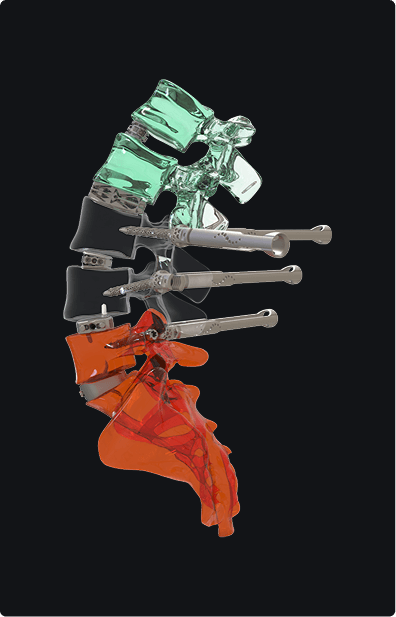

Is a company founded in 1997, initially focusing on the manufacturing of invasive diagnostic devices as a subcontractor for major medical device manufacturers.

Over the years, Tsunami Medical has grown and expanded its expertise in the medical field. Notably, the company acquired the Bloodline trademark, a well-established name in the international biopsy and vertebroplasty spinal markets. This acquisition has enabled Tsunami Medical to strengthen its position in the industry, offering advanced solutions for spinal surgery, including biopsy instruments and systems for vertebroplasty. With years of experience and a commitment to innovation, Tsunami Medical continues to provide high-quality products and technologies to healthcare professionals worldwide.Want to know more about Akson Romania?